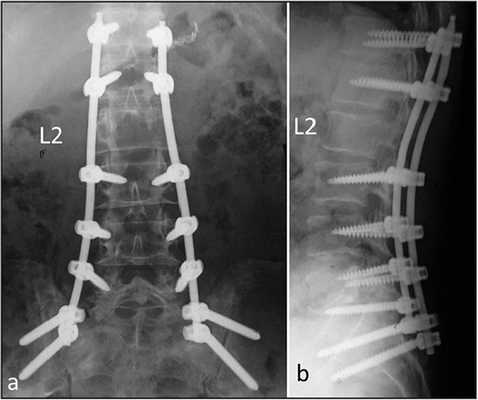

Обследовали 96 пациентов (в возрасте от 23 до 68 лет, из них 57 женщин и 39 мужчин), находившихся на лечении в нейрохирургическом отделении Краевой клинической больницы Красноярска с 2012 по 2016 г. и прооперированных повторно по поводу рецидивирующего дегенеративного поражения пояснично-крестцового отдела позвоночника. Из них 42 больным операцию выполняли из вентрального доступа с тотальной дискэктомией и установкой межтелового эндопротеза (1-я группа), 54 больным — ригидную транспедикулярную стабилизацию с межтеловым корпородезом кейджем и декомпрессией невральных структур из дорзального доступа (2-я группа).

В 1-й группе пациентов выполняли вентральный внебрюшинный доступ к уровню LV—SI, тотальную дискэктомию с передней декомпрессией дурального мешка, во 2-й группе — декомпрессию дурального мешка и корешков дорзальным срединным доступом с установкой межтелового кейджа и транспедикулярной винтовой фиксацией для формирования спондилодеза.

Во 2-й группе пациентов показатели угла операционного действия колебались от 79 до 95°, в среднем 87,1±8°. Угол оси операционного действия колебался от 75 до 89° и составил в среднем 82,1±4,1°. Длительность операции колебалось от 140 до 242 мин, в среднем 210±23 мин. Длина операционной раны колебалась от 80 до 140 мм, в среднем 108±14 мм. Глубина операционной раны колебалась от 70 до 130 мм и составила в среднем 103±21 мм. Кровопотеря колебалась от 80 до 760 мл, в среднем 440±23,5 мл. Такая большая кровопотеря обусловлена работой в эпидуральном пространстве с наличием большого количества расширенных эпидуральных вен на фоне рубцово-спаечного процесса.